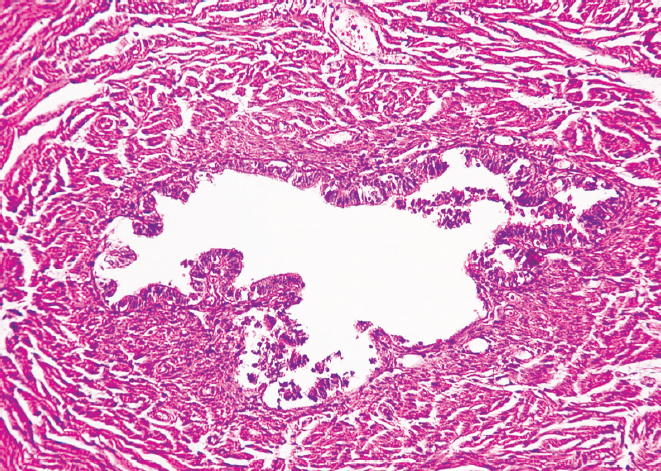

RESULTS: There was a decrease in the external diameter of the isthmus and funnel of both fallopian tubes in women from young age to old age (p < 0.01). At old age, there was a predominance of external diameter parameters of the isthmus and funnel of the right fallopian tube in comparison with those of the left fallopian tube (p < 0.01), while at young age there was only a tendency for the diameter of the isthmus and funnel of the right fallopian tube to predominate (p > 0.05). The histological study showed the presence of thickened folds of the mucous membrane and flattened epithelium in the studied areas in older women, thinning of the muscular membrane layers and overgrowth of connective tissue in comparison with the samples taken for the study in younger women.

CONCLUSIONS: Morphologic restructuring of the isthmus and funnel of the fallopian tubes from young to old age consists in thickening of the mucous membrane folds, flattening of the epithelium, overgrowth of connective tissue in the wall and reduction of their outer diameter with predominant parameters in the right fallopian tube.